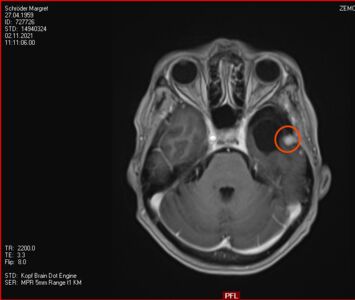

Ich fühle mich gesund und fit und so ein Tumor im Hirn tut nicht weh. Am 2. November ist wieder ein MRT dran und es wird sich zeigen, wie sich der Tumor entwickelt hat. Gestört hat er in den letzten Monaten nicht - jedenfalls nicht für mich erkennbar. Trotzdem ist es immer etwas aufregend, wenn der Blick ins Gehirn ansteht und etwas zu Tage kommen könnte, das ungewisse Konsequenzen haben könnte.

12. November 2021: Innerhalb der Messungenauigkeit

Heute war ich mit Stephan in der Ambulanz der Neurochirurgie zur Auswertung des MRTs, dass vor 10 Tagen erstellt wurde. Das Ergebnis ist erfreulich:

- der Tumor ist sehr klein (< 10mm) und deshalb stört er nicht

- der Tumor ist, wenn überhaupt, sehr wenig gewachsen und so genau misst das Gerät nun auch nicht (vielleicht habe ich nicht still gelegen?!)

- durch die Gamma-Knife-Bestrahlung kann man das Wachstum des Tumors beschränken, die Strahlen entfernen ihn nicht

- falls doch mal Wachstum auftreten sollte, sitzt das Ding an einer guten Stelle und aus Sicht des Neurochirugen ist es "im Notfall" nur eine kleine Sache ihn zu entfernen

Also alles prima, alle Aufregung unnötig. Ich lebe nun halt mit einem Tumor im Kopf weiter und lassen ihn in 6 Monaten neu inspizieren. Ich bin erleichtert, es geht mir prima und auch die Schulternschmerzen haben sich verzogen. Gestern konnte ich auch schon wieder 15km langsam joggen.

2. November 2021: Leider etwas gewachsen

Heute war ich im MRT im Bremen. Der Befund des auswertenden Arztes ist, dass er der Meinung ist, dass der Tumor etwas gewachsen ist. Ich habe mir die Bilder angesehen und versucht diese Aussage zu verstehen. Vermutlich ist sie richtig, aber das Wachstum ist nicht heftig nur vielleicht von 0,7 cm auf 0,8 cm. Aber Gamma-Knife hat es offensichtlich nicht entfernt.